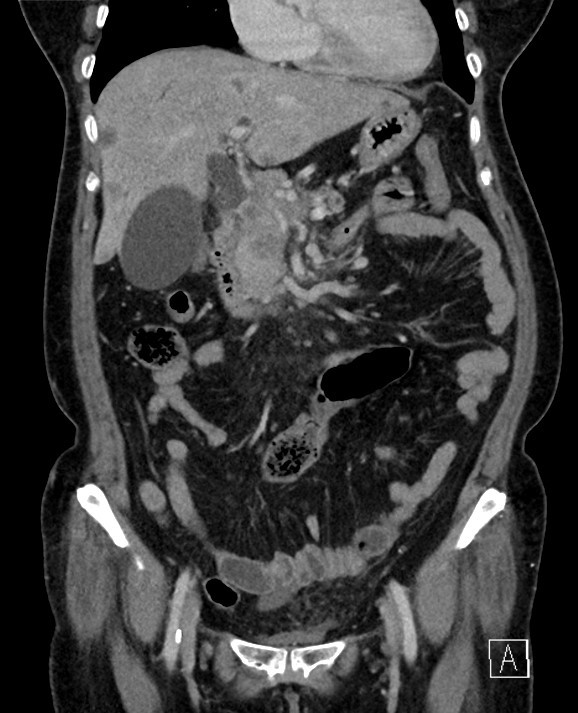

66세 남자가 3일 전부터 얼굴이 노래지고 소변색이 진해져서 응급실에 왔다. 최근 1개월간 몸무게가 9 kg 정도 빠졌다고 한다. 혈압 130/80 mmHg, 맥박 96회/분, 호흡 20회/분, 체온 36.3 ℃이다. 온몸과 공막이 노랗다. 배에 압통이나 반동압통은 없다. 이전 수술력은 없다고 한다. 혈액검사 결과는 다음과 같다. 복부 컴퓨터단층촬영 사진이다. 조치는?

CT: Distal CBD mass, upstream biliary dilatation, GB dilatation, multiple low-attenuating hepatic lesions

Imp: 원위부 담관암(distal cholangiocarcinoma)

임상양상 및 CT 소견으로 보아 distal cholangiocarcinoma가 강력히 의심되며, 현재 정체된 담즙을 급하게 배액하기 위한 ERCP가 필요하다.

• CT상 distal CBD에 종양이 확인되며, 이보다 upstream하게 CBD와 GB가 늘어난 것이 보인다. 또한 간에 저음영 nodule이 몇 개 보이는데, 이는 distal cholangiocarcinoma의 간 전이를 시사한다.

• 따라서 본 환자의 cholangiocarcinoma는 unresectable할 가능성이 매우 높으며, 따라서 근치적 치료보다는 현재 가장 큰 문제인 biliary obstruction을 해소하기 위한 완화적 치료가 필요하다. 따라서 내시경역행담관조영(endoscopic retrograde cholangiopancreatography, ERCP)을 통해 stent 삽입 등을 이용한 배액을 시도해야 한다.